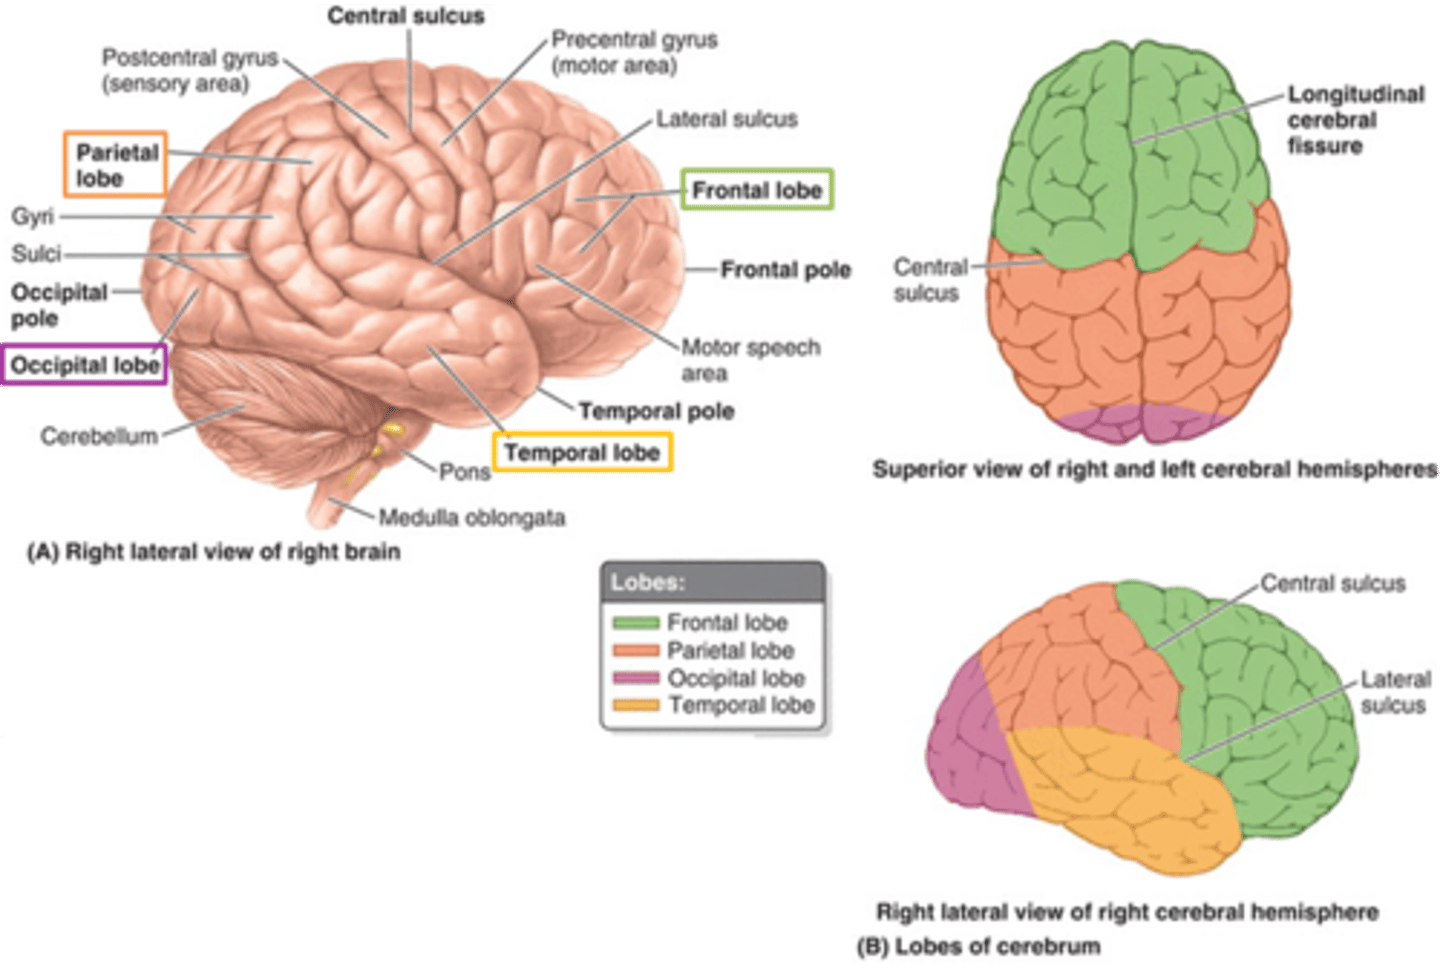

what are 3 key white matter structures found in the cerebrum?

1. corpus callosum

2. corona radiata

3. internal capsule

what cerebral white matter structure is a large bundle of nerve fibers that connects the left and right cerebral hemispheres, allowing them to communicate?

corpus callosum

what is the fan-shaped cerebral white matter sheet that is continuous ventrally with the internal capsule?

corona radiata

what cerebral white matter structure is a tract that carries sensory and motor information to and from the cerebral cortex?

internal capsule

what cerebral white matter structure is found between the basal ganglia?

internal capsule

what are the 3 regions of the internal capsule?

1. anterior limb

2. genu

3. posterior limb

what cerebral gray matter structure is a collection of subcortical nuclei primarily involved in motor control?

basal ganglia

what cerebral gray matter structure has a gate-keeping mechanism for the initiation of motor movement (choosing which actions to allow and which to inhibit)?

basal ganglia

what cerebral gray matter structure has roles in motor learning, executive functions, behaviors, and emotions?

basal ganglia

what are the 3 parts of the basal ganglia? what runs between them?

1. caudate nucleus

2. putamen

3. globus pallidus

internal capsule

what part of the basal ganglia is the C-shaped structure that is most medial?

caudate nucleus

what part of the basal ganglia is medial to the putamen?

globus pallidus

the putamen and globus pallidus of the basal ganglia are collectively called the _______________ nucleus

lentiform